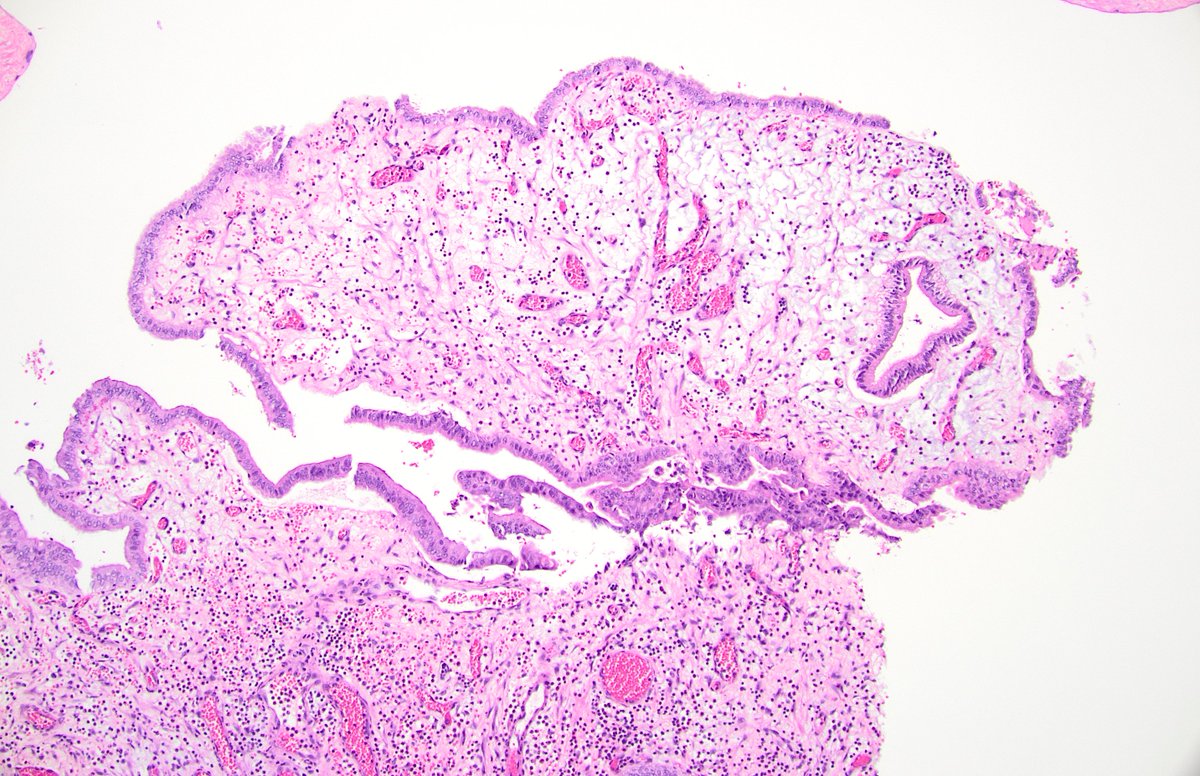

@forthejon @et565 On morphology I would have gone for HG dysplastic naevus. PRAME and molecular seem to point in the same direction here and what you have said is v reasonable. Management is the same - wider excision.

#WhatsNewInDermpath Utilizing PRAME expression and a meta-analytic framework for iSALT to explore atypical late-onset nevi of the elderly and their relationship with lentiginous and nested nevoid melanomas journals.lww.com/amjdermatopath…